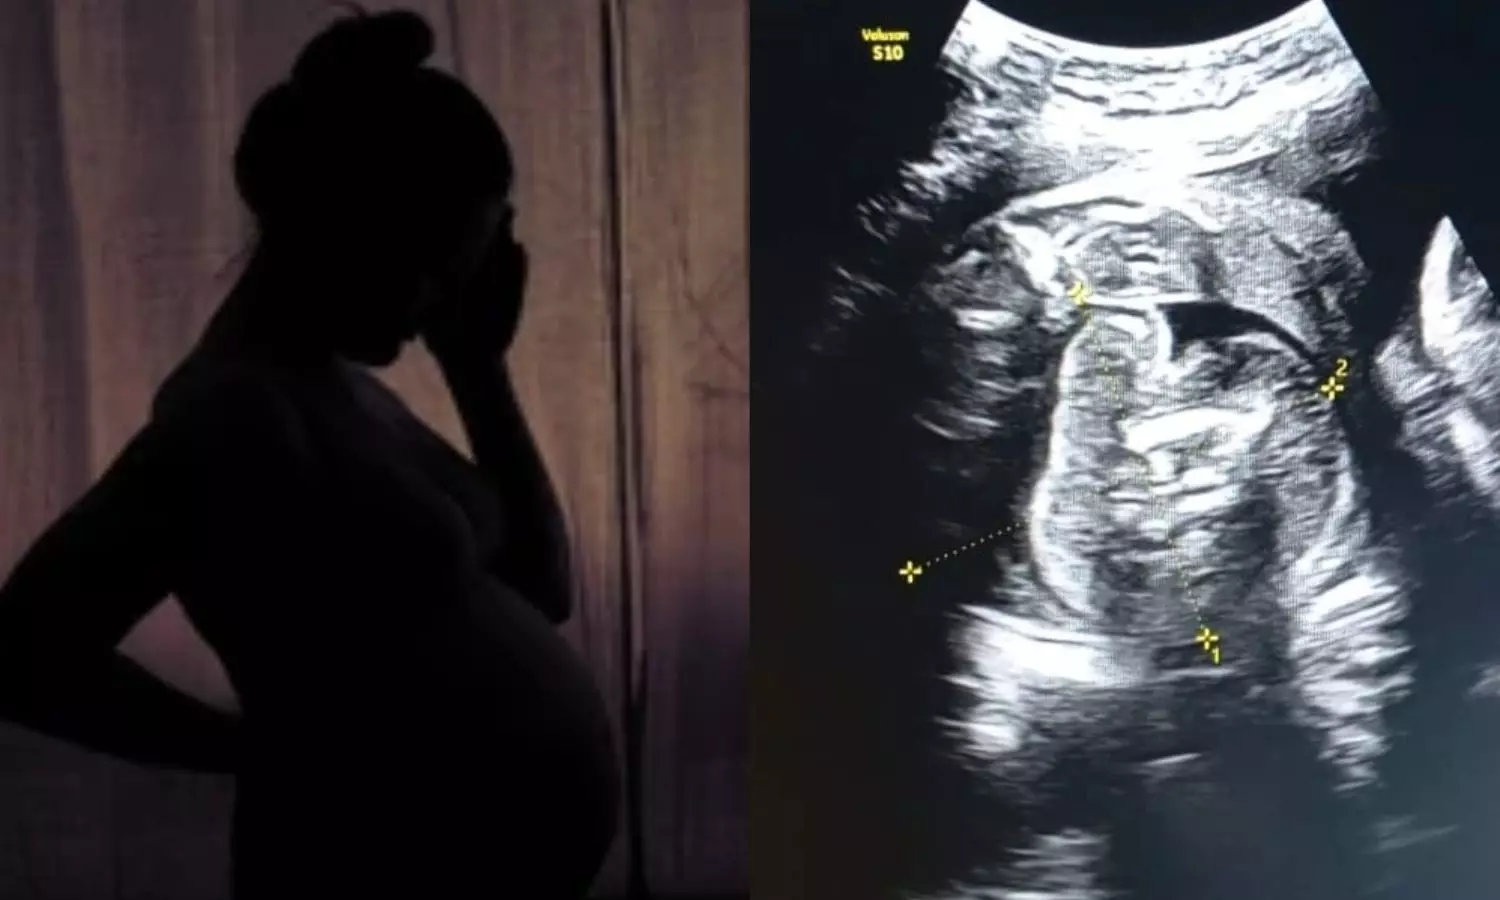

கர்ப்பிணிப் பெண்ணின் வயிற்றில் உள்ள குழந்தைக்குள் வளரும் கரு.. ஆச்சர்யத்தில் மருத்துவர்கள்!